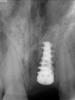

samsonov Опубликовано 22 мая, 2012 Поделиться Опубликовано 22 мая, 2012 Приветствую всех.Пришёл сегодня пациент с безымянным имплантом.Чует моё сердце- АВ? Ссылка на комментарий

samsonov Опубликовано 22 мая, 2012 Поделиться Опубликовано 22 мая, 2012 (изменено) похож Спасибо за "сочуйственность"! Будем ставить формирователь,значит... Изменено 22 мая, 2012 пользователем samsonov Ссылка на комментарий

КДБ Опубликовано 23 мая, 2012 Поделиться Опубликовано 23 мая, 2012 Приветствую всех.Пришёл сегодня пациент с безымянным имплантом.Чует моё сердце- АВ? да и на НИКО(лидер)смахивает Ссылка на комментарий

samsonov Опубликовано 6 июня, 2012 Поделиться Опубликовано 6 июня, 2012 точно АВ"Вскрытие" подтвердило предварительный диагноз- АВ.)))Стася,Вита,КДБ ---- спасибо большое. Ссылка на комментарий